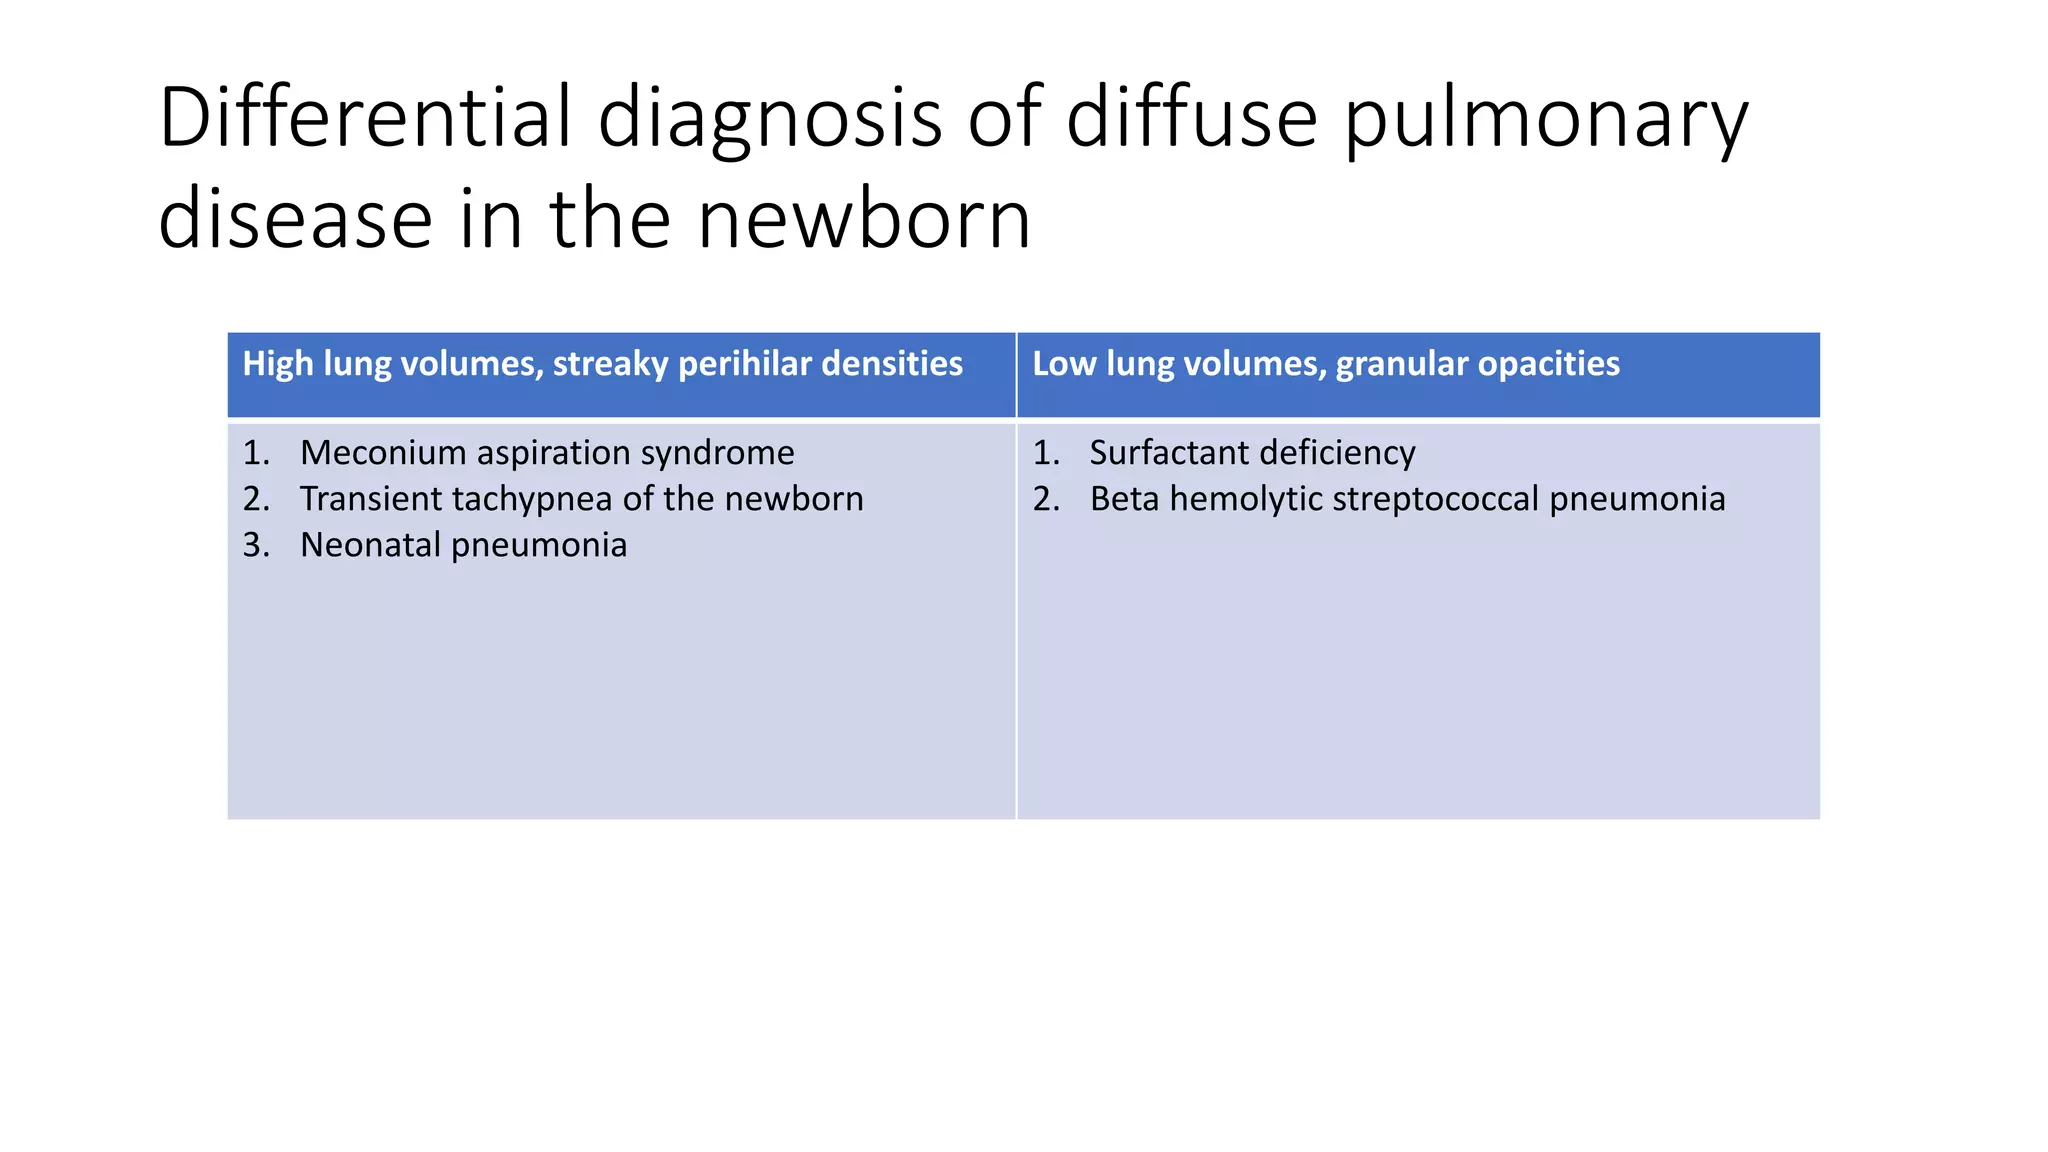

This document provides an overview of neonatal chest x-rays, including when they should and should not be performed, what a normal x-ray looks like, common positions of tubes and catheters, and common causes of respiratory distress in neonates. It discusses the appearance of a normal chest x-ray as well as conditions like respiratory distress syndrome, transient tachypnea of the newborn, meconium aspiration syndrome, and pneumonia. Surgical conditions like diaphragmatic hernia and esophageal atresia are also reviewed.